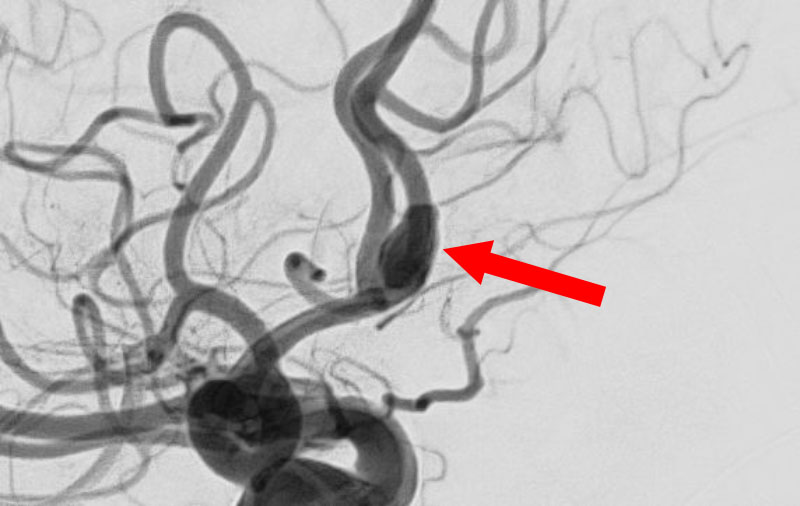

'25年11月

くも膜下出血

右内頚動脈後交通動脈

分岐部動脈瘤破裂

60代

救急外来

No.1593 手術前

No.1593 手術中

No.1593 手術後